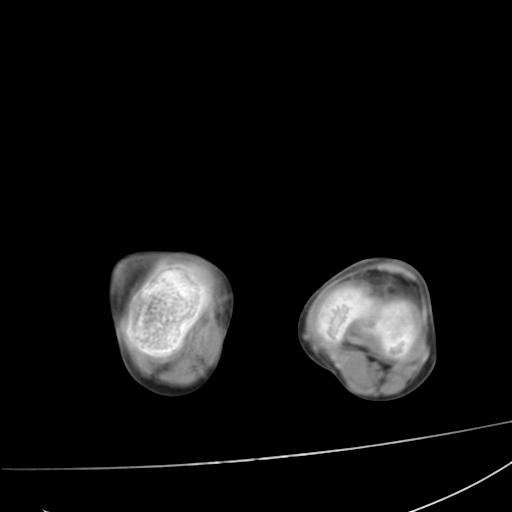

标题: PED0940:M12Y,左股骨下端酸痛畸形 [打印本页]

标题: PED0940:M12Y,左股骨下端酸痛畸形

12岁男孩,左膝关节肿痛8年,近月明显

内生骨软骨瘤?

血友性关节病?